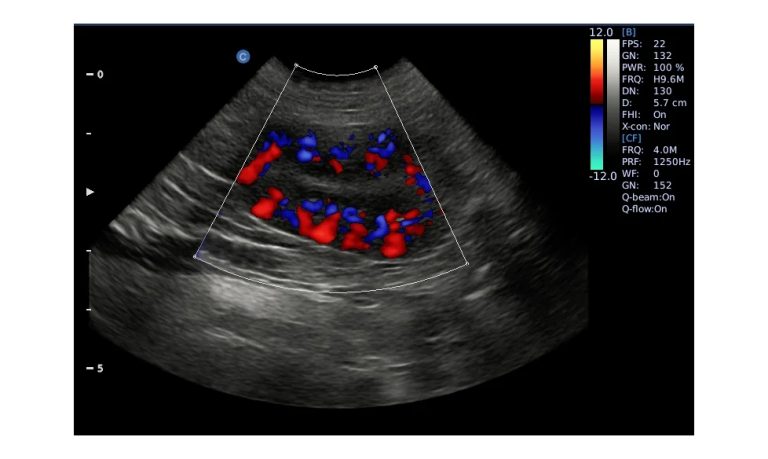

Ultrasound

Wide range of Ultrasound machines that suites a variety of applications from abdominal to rectal scans, we take in consideration how the world is moving towards mobility and mobile applications.

SonoBook

Smart Laptop with Premium Performance

Genius Light Powerful Thin Accurate Fast Quickly

All The Aspects Are Ready To Go